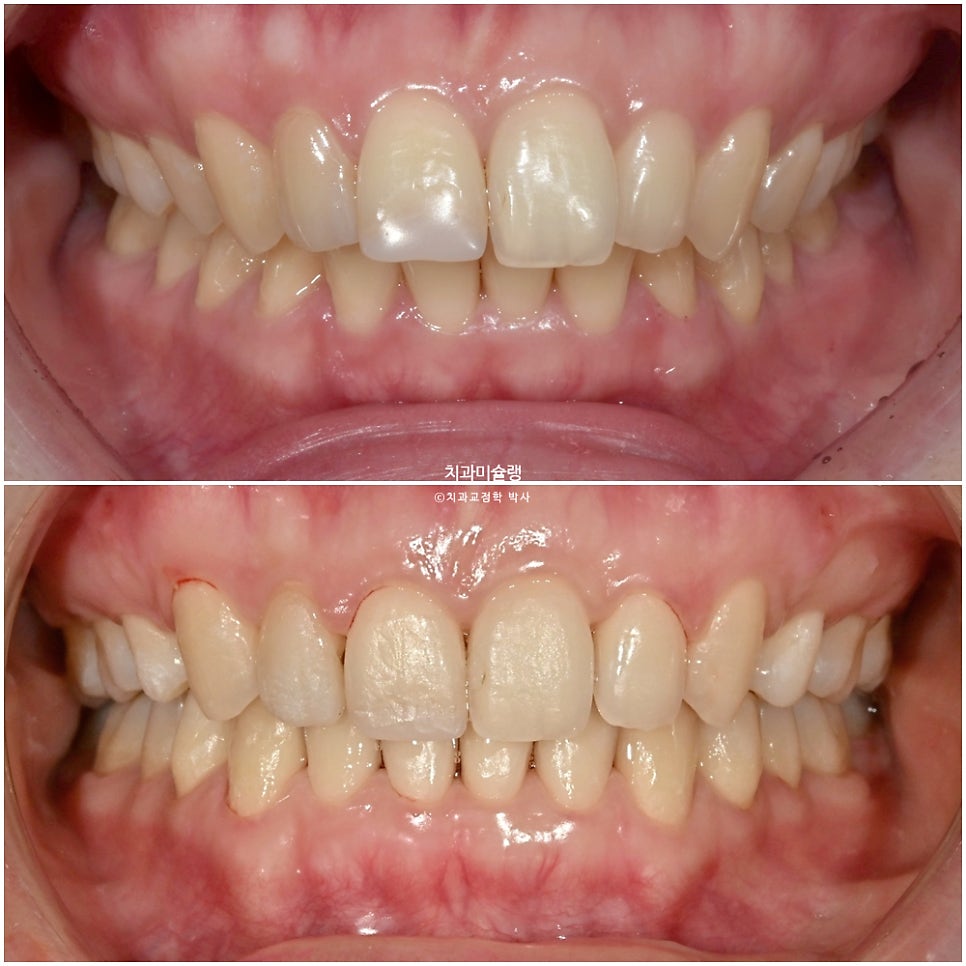

23년 4월, 교정치료를 위해 오신 20대후반 환자입니다. 실제론 앞니가 전반적으로 작은편임에도 불구하고 사진에서 앞니가 유독 커보이는건 돌출되어있기 때문입니다.

치열은 정면에서 볼때 원근법을 따르기에 튀어나와있으면 커보이고 뒤로갈수록 작아보이죠.

앞니 2개가 유난히 돌출되어 있습니다.

이제 전후 비교 보겠습니다.

초진사진에서는 가운데 앞니가 커보였으나 교정후 사진에서 가운데앞니가 작아진것처럼 보이죠.

하지만 앞니 사이즈가 작아진게 아니라, 튀어나와있던 앞니가 뒤로 들어가며 비로소 본래 사이즈로 보이는것이랍니다.